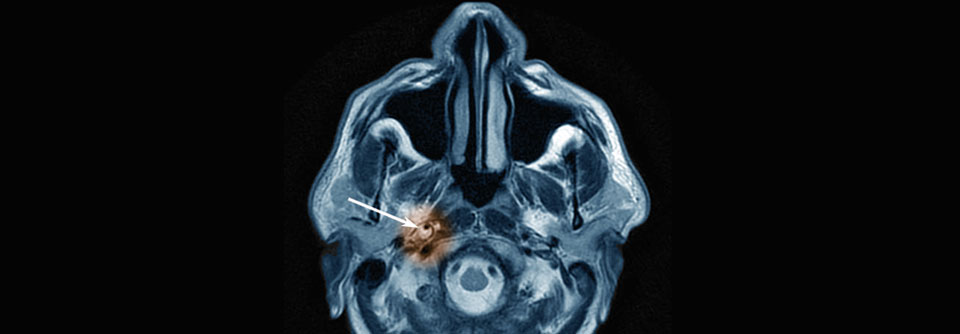

ASS schützt nach einem arthroplastischen Eingriff an Hüfte oder Knie so gut vor Thromboembolie wie direkte orale Antikoagulanzien. ASS schützt nach einem arthroplastischen Eingriff an Hüfte oder Knie so gut vor Thromboembolie wie direkte orale Antikoagulanzien. © fotolia/Axel Kock